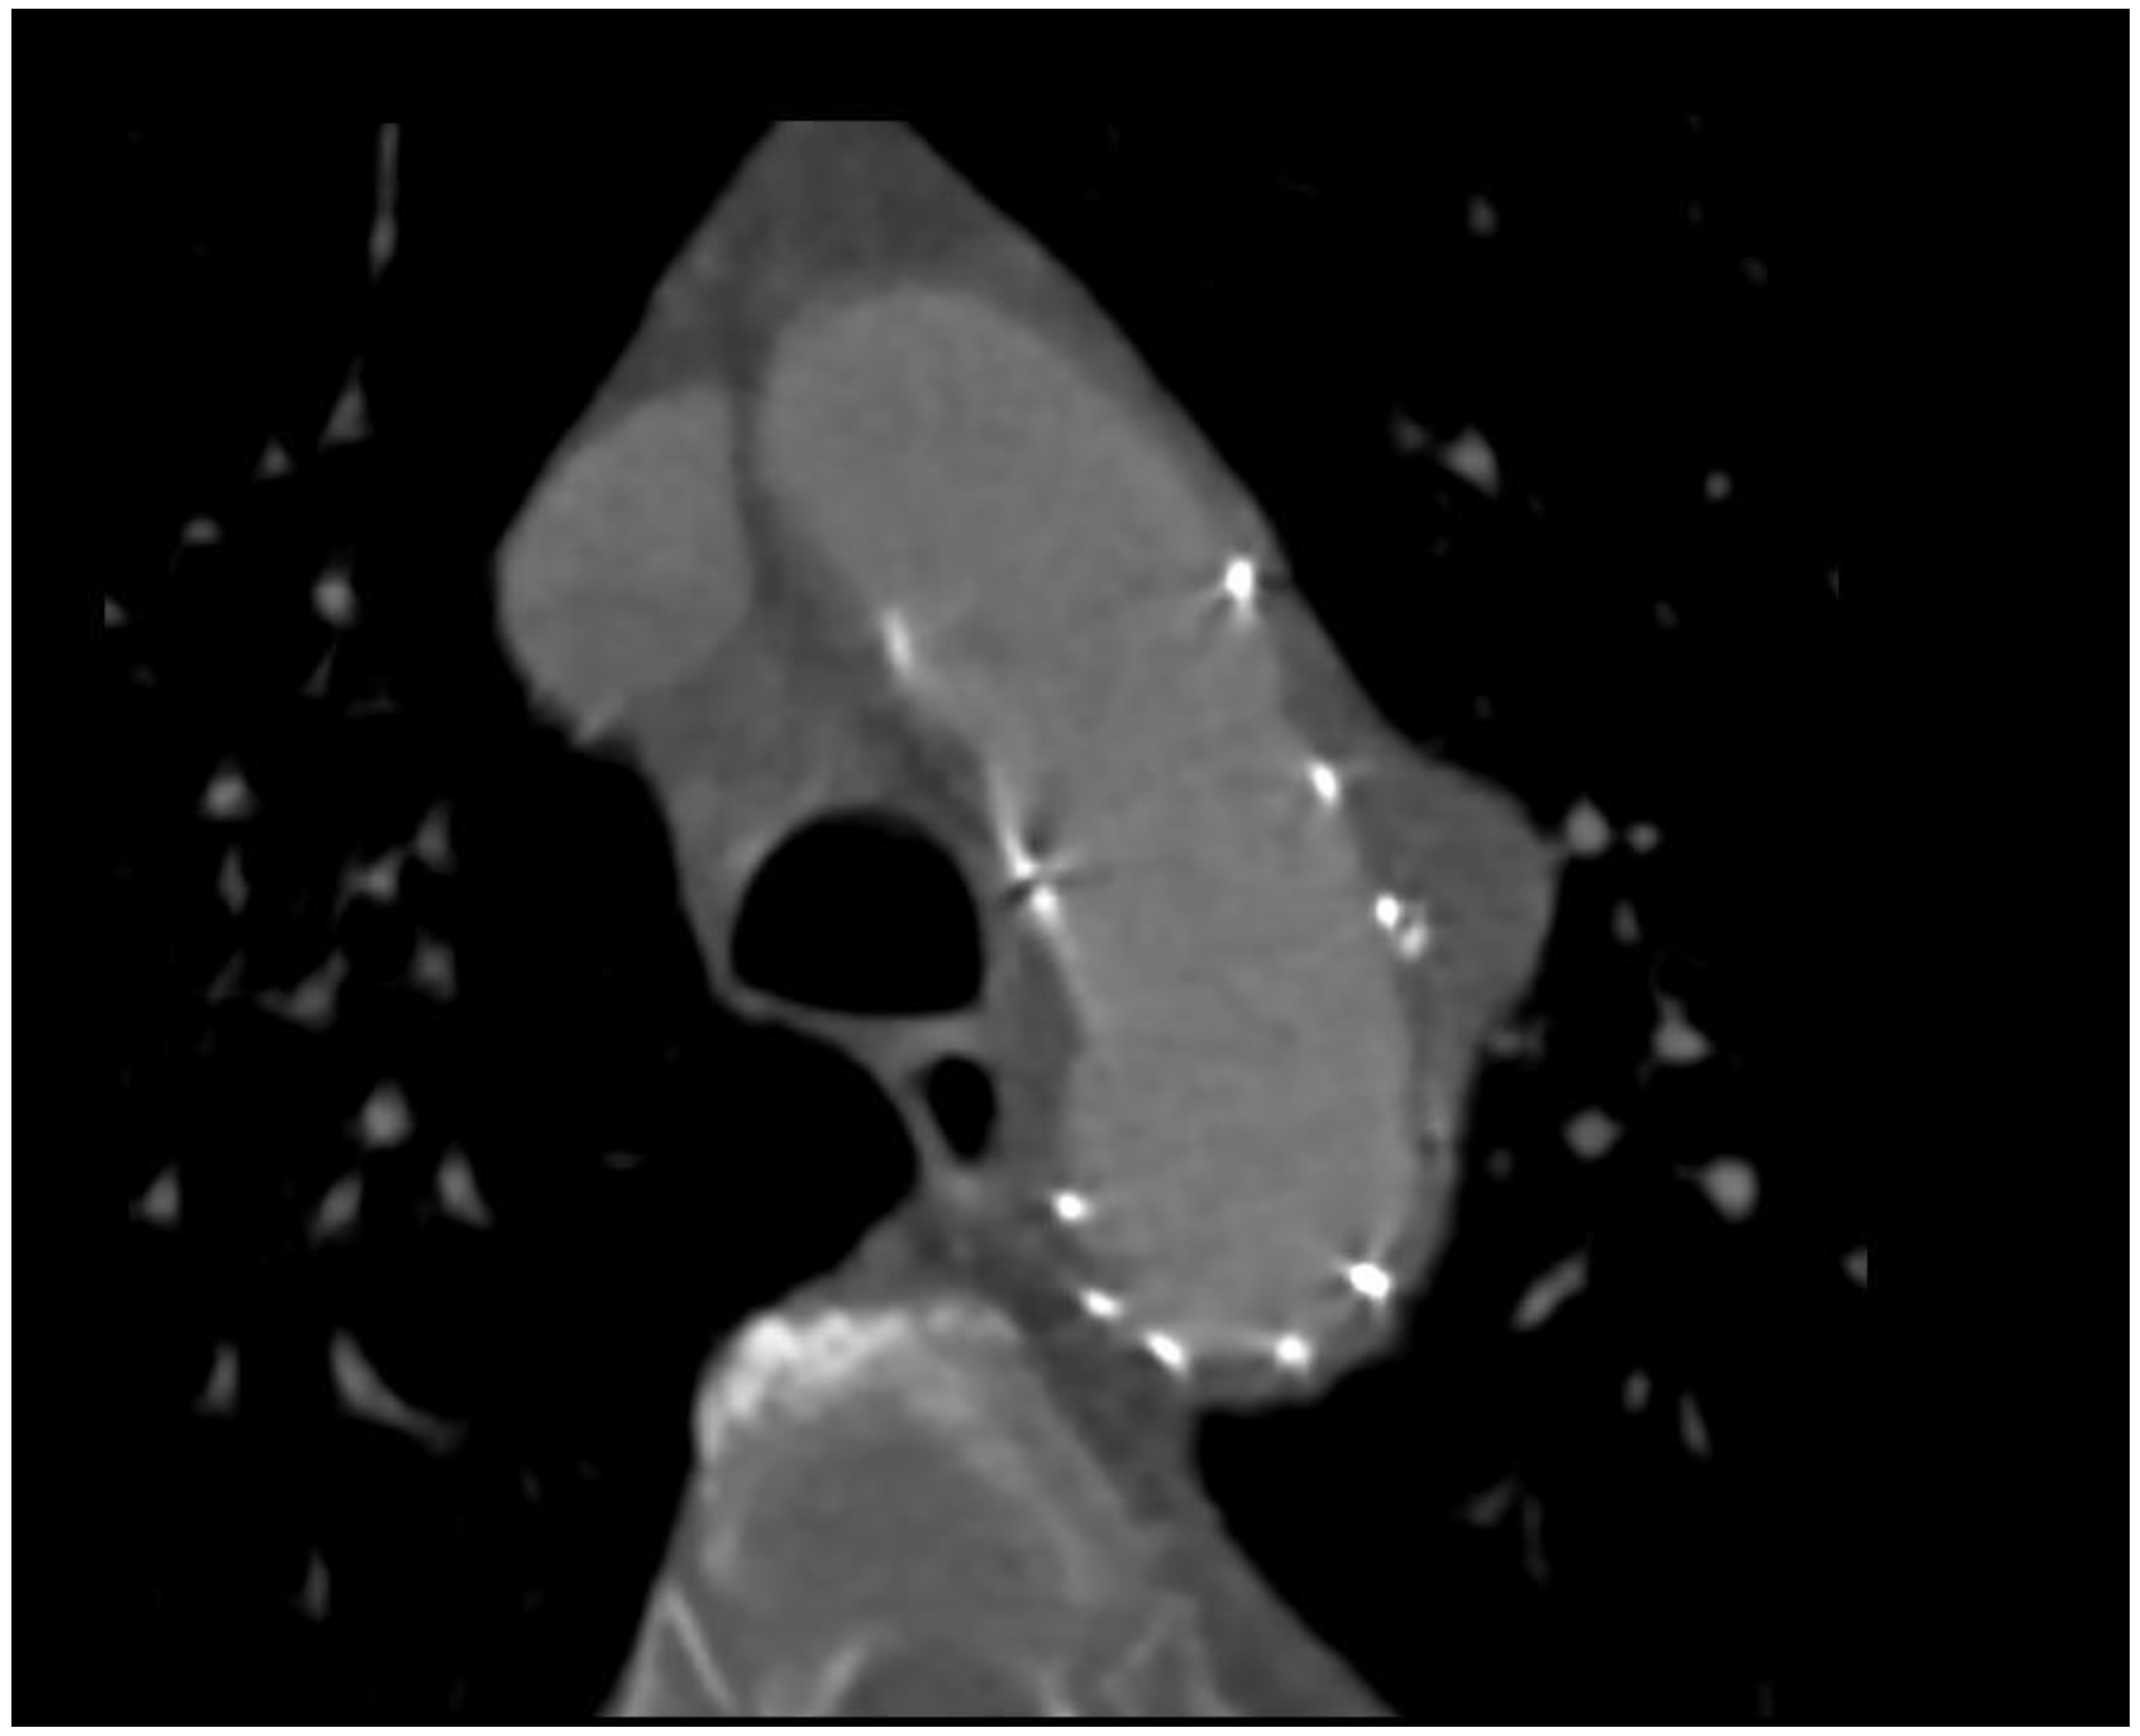

2. Case 1

A 79-year-old man with arterial hypertension, carotid artery stenosis and previous subdural hematoma presented in our hospital with an episode of transient chest pain radiating to his back; computer tomography showed this to be a penetrating aortic ulceration. After 2 years of follow up, the last computed tomography (CT) revealed intimal ulceration in the aortic arch. The lesion, a penetrating atherosclerotic ulcer, affected the left aspect of the patient’s aortic arch with diameter of 46 mm × 22 mm and height of 21 mm (Figure 1 and Figure 2), then the risk of progression to frank aortic dissection was large. Both the innominate artery and the left carotid artery were patent and free of dissection. The patient’s surgical risk was calculated as moderate–high, and thus we decided to perform an endovascular approach.

Figure 2. Preprocedural 3D CT; red arrow shows PAU.